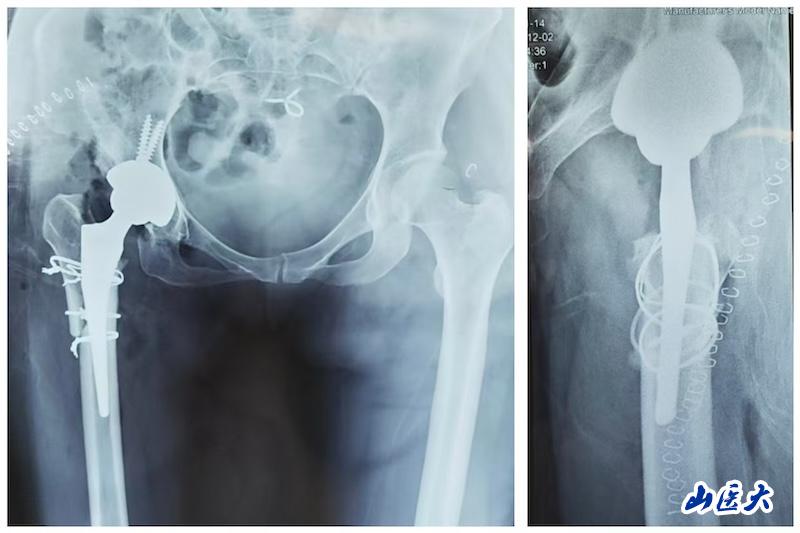

李春江主任团队采用的股骨近端截骨重建技术(亦称“尚氏截骨”),通过在粗隆间行长斜形截骨,重塑股骨近端形态,在矫正复杂畸形、调整肢体长度的同时,实现了“远端压配、近端适配”的稳定固定。该术式最大限度保护髋外展肌,截骨面接触广泛,骨愈合率高,为复杂髋关节畸形的重建提供了可靠选择。

术后影像显示,该患者髋臼重建于真性髋臼,旋转中心得到恢复;股骨侧通过截骨重建,使用普通全涂层假体,同步矫正畸形、恢复偏心距,实现双下肢等长。